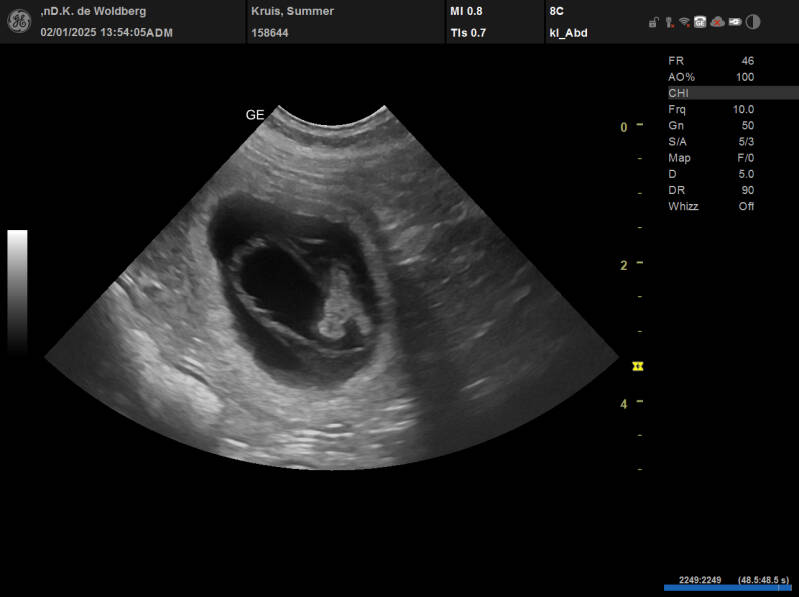

De Echoscopie van de Dracht

Het drachtige buikje